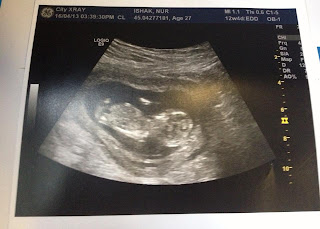

Honey E at 12 weeks ++

Heee alhamdulillah